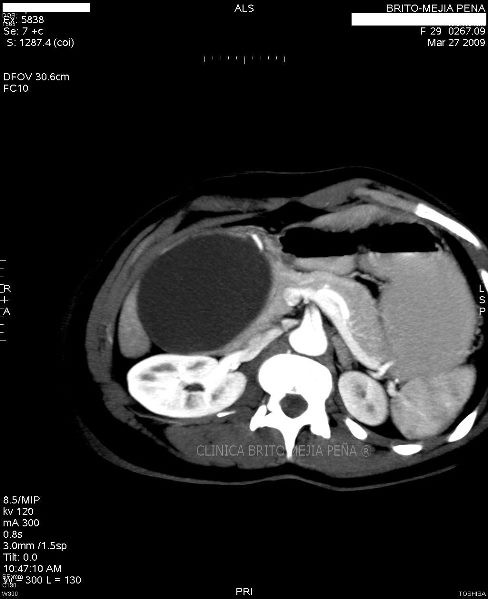

Metástasis hígado fase arterial